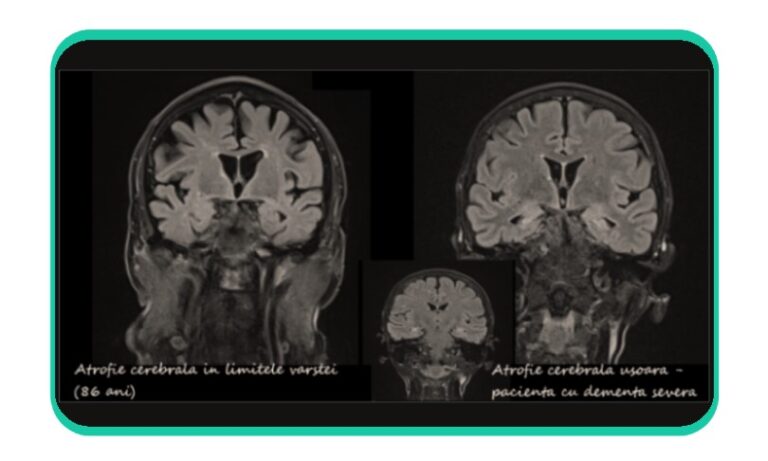

Dementa, prin tulburarile de memorie si de judecata logica, reprezinta o suferinta deseori asociata cu atrofie cerebrala, in cadrul bolilor neurodegenerative. Atrofie cerebrala denumeste scaderea volumului creierului. Acesta nu este un diagnostic.

Atrofia cerebrala poate fi descrisa in evolutia tardiva a multor afectiuni ale sistemului nervos. Aceasta poate fi generalizata sau localizata si asociaza de obicei largirea compensatorie a spatiilor lichidiene intracerebrale, ventriculomegalie. In acest caz, cresterea dimensiunilor ventriculilor cerebrali nu este consecinta unui dezechilibru in producerea sau resorbtia lichidului cefalorahidian, adica nu este hidrocefalie. Ventriculomegalia este secundara reducerii volumului “tesutului cerebral”.

Deseori, vorbim despre atrofie in raport cu varsta, la persoane varstnice fara dementa. Pentru a stabili o corelatie intre aspectul cerebral si dementa, este necesara interpretarea corecta si a celorlalte leziuni observabile.

In concluzie, nu exista o corelatie directa intre prezenta unei descrieri de atrofie cerebrala si dementa prezenta sau iminenta. Atrofia cerebrala nu reprezinta neaparat element predictiv pentru dementa.